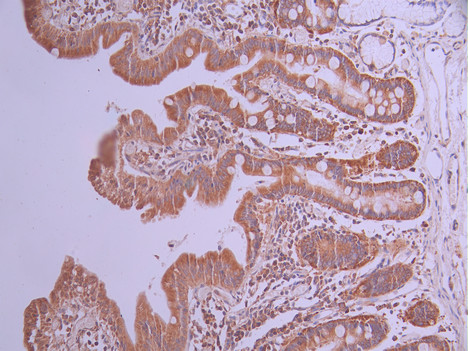

IHC image of CSB-RA258376A0HU diluted at 1:100 and staining in paraffin-embedded human small intestine tissue performed on a Leica BondTM system. After dewaxing and hydration, antigen retrieval was mediated by high pressure in a citrate buffer (pH 6.0). Section was blocked with 10% normal goat serum 30min at RT. Then primary antibody (1% BSA) was incubated at 4°C overnight. The primary is detected by a Goat anti-rabbit polymer IgG labeled by HRP and visualized using 0.05% DAB.